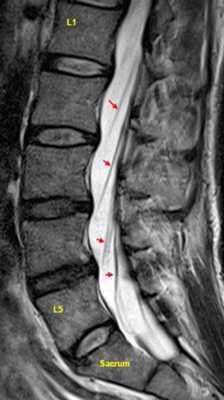

МРТ позвоночника. Парасагиттальная (околосрединная) Т2-взвешенная МРТ поясничного отдела. Красными стрелками показаны корешки.

После того, как появилась ясность в способе получения МРТ изображений позвоночника, надо понять какие анатомические структуры видны. Счет позвонков ведется разными способами - сверху от зубовидного отростка С2 (осевой позвонок), от бифуркации трахеи Т5 ( пятый грудной, с погрешностью на 1 позвонок) или снизу от L5 (последний поясничный), также не исключена погрешность на 1 позвонок в связи люмбализацией или сакрализацией. Анатомия позвоночника в МРТ изображении представлена в нашей другой статье. На серии сагиттальных Т2-взвешенных МРТ позвоночника видны асе основные структуры, причем удается проследить ход корешков конского хвоста. В поясничном отделе он идет под углом вниз и выходит через межпозвоночное отверстие нижележащего позвонка. Аксиальные (поперечные) МРТ срезы всегда делаются вдоль межпозвоночного диска, то есть с учетом нормальных или патологических изгибов позвоночника. Они наиболее удобны для оценки состояния дугоотростчатых суставов. При МРТ позвоночника в поперечной плоскости МРТ срезы часто делают на разных уровнях для лучшей визуализации состояния корешков по их ходу - в дуральном мешке, затем боковом кармане дурального мешка, далее в межпозвоночном отверстии и, наконец, после выхода из него. Таким образом, в поперечном МРТ срезе позвоночника через межпозвоночное отверстие на поясничном уровне можно видеть отрезки сразу двух корешков - вышележащего на выходе из отверстия, и нижележащего в боковом кармане.